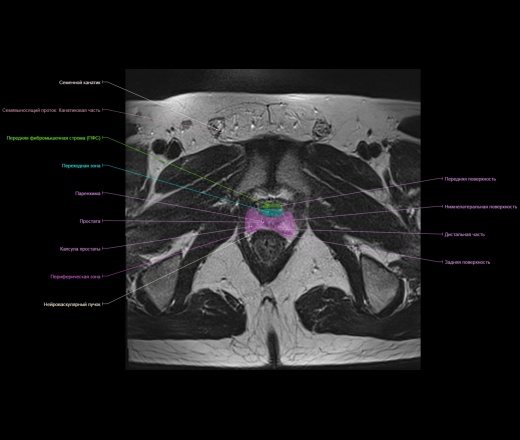

Представленный материал носит обучающий характер, не стал размещать в разделе Презентации, из за отсутствия вьюера с возможностью именно прокручивать изображения как на рабочей станции.

Надписи очень плохо видно, разместил в разделе Презентации там видно получше.

Основная задача исключить или выявить и стадировать рак предстательной железы. Урологи направляют пациентов с высоким уровнем PSA (простат-специфический антиген). До проведения МРТ может быть выполнено ТРУЗИ. МРТ простаты должна быть мультипараметрической, т.е. стандартные взвешенные импульсные последовательности Т2 c полем обзора (FOV) не более 180 мм, Т1, диффузионно-взвешенные изображения DWI и динамическое контрастное усиление ДКУ, при наличии соответствующего программного обеспечения МР-спектроскопия.